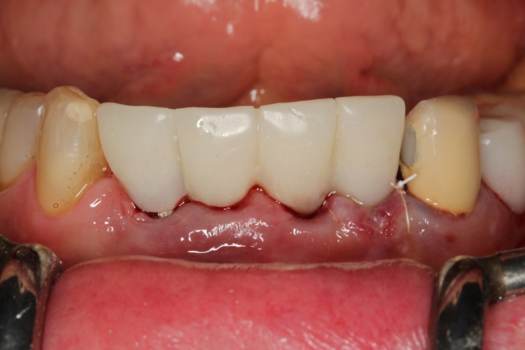

Fig 44. Splinted PMMA seated.

Figure 44

Fig 45. Occlusal view of seated PMMA provisionals.

Figure 45

On the day of surgery, the plan was to extract teeth Nos. 21, 23, 24, 25, and 26, place 3.0 x 13-mm implants in the anterior region due to limited spacing, and place a 4.1 x 10-mm implant in the No. 21 extraction site. Before the extractions were performed, the No. 23 pontic was sectioned from the existing 2-unit cantilevered bridge utilizing ceramic and metal high speed rotary cutting burs ZR 6881 and H34L (Komet-USA), respectively. After removal of the pontic and extractions, the surgical guide was verified to be seating positively (Figure 36 through Figure 38). Surgical guide protocol was followed, and all implants were successfully placed and torqued to a value of greater than 35 Ncm (Figure 39 and Figure 40). All implants were placed without flapping, with the exception of No. 23. The flap was elevated to reposition lingual keratinized tissue facially for enhanced esthetic tissue profile. The implants were then prepared with a high-speed carbide bur (Komet-USA) with copious amounts of water (Figure 41 and Figure 42). The one-piece 3.0-mm diameter implant served the needs of the patient's spacing requirements. Inter-occlusal space requirements and path of draw were verified. The PMMA provisionals were air abraded and relined with crown-and-bridge material (Figure 43 through Figure 45).

Due to the guided surgical and prosthetic protocol, this case was completed with tissue sparing and atraumatic extractions with precision implant placement. The most arduous task of the entire procedure was the physical implant abutment preparation for proper clearance. If the patient had more space to plan her treatment, implants using a two-piece protocol would have been implemented with screw-retained non-engaging provisionals after implant placement. Again, this decision process is solely in the hands of the clinician providing services.